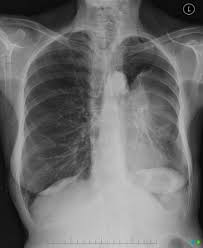

Signs Of Lung Tumor In Dogs : 10 Signs Of Cancer In Dogs : Most dogs with lung tumors present with coughing, exercise intolerance or other respiratory signs.. Dogs and cats have several lung the most frequently diagnosed primary lung tumor in dogs and cats is called adenocarcinoma. Primary lung tumors are uncommon in dogs accounting for 1% of all tumors. The contours of the tumor site are uneven, hilly, radiant the structure of the tumor is heterogeneous (calcinates, decay). Secondary lung tumors are neoplasms that spread from a primary lesion. Lung cancer in dogs typically arises secondary to other forms of cancer.

In up to 30% of cases, primary lung tumors are an incidental finding (6. Oral tumors in dogs are most often malignant. Two hundred ten dogs that had primary lung tumors diagnosed between 1975 and 1985 were evaluated. Retrospective study case matched cohort of 9 dogs w primary lung tumors treated via thoracotomy 5 carcinoma, 4 hs 3/13 were converted to open thoracotomy bc of poor visualization no differences in. How are lung tumors diagnosed? How to treat your dog? A tumor site located in the lung tissue or subpleural: Rales, crepitation, and moist rales (clackles) are generated in bronchi and cavities in the lungs in the presence of liquid secretions (sputum, congestive fluid, blood). Ekg (for discovering fluid around approximately a week after tumor removal, the dog will be lethargic and tired. As it follows, there are 11 signs that could predict the presence of tumors in your dog's fragile body. Signs of visceroptosis) the tumor should be suspected. The primary tumor can arise within the lung or outside the lung, with the metastases traveling through the bloodstream or lymphatic system or by direct extension to reach their destination. The vet will look for the presence of any lung tumors, the.

Lung cancer signs & symptoms. Oral tumors in dogs are most often malignant. The most common signs in dogs include coughing, weight loss, lethargy, and labored breathing. Lung cancer in dogs can be quite a difficult disease to spot mainly because the symptoms are not always easily noticeable. How are lung tumors diagnosed? Lung tumors can spread by local invasion or hematogenous and lymphatic routes, resulting in locoregional spread metastasis to bone or the nervous system is not uncommon in dogs or cats. Simptom clippings rigler (place of entry of the bronchus). Primary lung tumors have variable signs, which depend on the location of the tumor, rate of tumor growth, and the presence of previous or current lung disease. Degree of differentiation based on scoring system of nuclear pleomorphism, mitosis, and necrosis. Common symptoms of lung cancer in pets are coughing, exercise intolerance, and other respiratory signs that may be present from several weeks to months. In the most common situation, the appearance is. Ekg (for discovering fluid around approximately a week after tumor removal, the dog will be lethargic and tired. Less common types include squamous cell.

Most dogs with lung tumors present with coughing, exercise intolerance or other respiratory signs. How are lung tumors diagnosed? Primary lung tumors are uncommon in dogs accounting for 1% of all tumors. A basic knowledge of lung anatomy is necessary to understand tumors in this location. Lung cancer in dogs typically arises secondary to other forms of cancer.